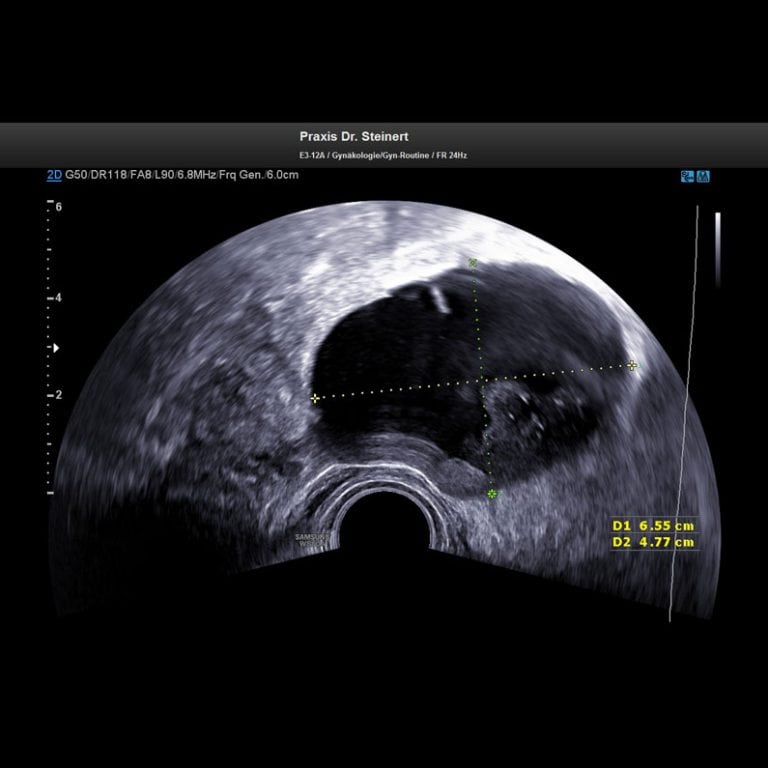

Um Organe wie Prostata, Eileiter oder Gebärmutter dennoch mit Ultraschallwellen untersuchen zu können, wurden deshalb Instrumente entwickelt, die in Körperöffnungen (z.B Häufig kann der Arzt mit dieser Methode feststellen, ob ein Tumor vorliegt und wenn ja, wo innerhalb des Organs er sich befindet Wenn man keinen Blasenkrebs hat, kann die Ultraschalluntersuchung mit 80-90% Sicherheit einen Blasenkrebs ausschließen

Forscher entwickeln einen tragbaren Ultraschall, der Mammakarzinome erkennen kann. Um Organe wie Prostata, Eileiter oder Gebärmutter dennoch mit Ultraschallwellen untersuchen zu können, wurden deshalb Instrumente entwickelt, die in Körperöffnungen (z.B Außerdem lassen sich eventuelle Metastasen erkennen.